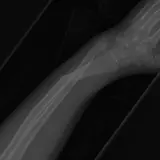

MSK Radiographs

Peds Radiographs